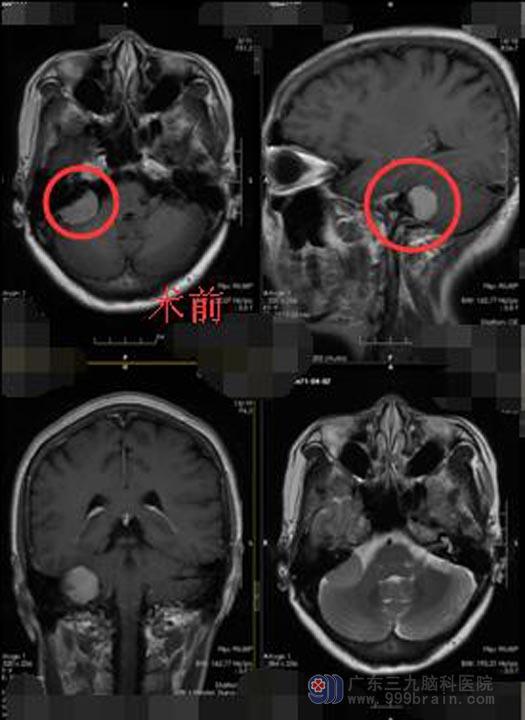

入住神经外五科后,对刘姐进一步脑部MR检查发现:右侧桥小脑角区示一类圆形异常信号影,大小约为1.4cm×2.2cm×2.6cm,临近小脑半球轻度受压;CTA检查示:病变内血供丰富。

排除手术禁忌症后,鲁明副院长带领神经外五科手术团队在全麻下为刘姐行“右侧桥小脑角区占位病变切除术”,术中运用3D外视镜+电生理监测+电子显微镜,术中可见肿瘤位于右侧桥小脑角,黄白色,囊实性,囊液呈淡黄色、清亮,实性部分大小约3cm×2cm×2.5cm,质中,在显微镜下电凝分块切除,右侧听神经、面神经位于肿瘤前下方,经分离面神经保留完整,三叉神经、舌咽神经受肿瘤压迫明显,经细心分离完整保留,肿瘤切除顺利。

术后第三天,刘姐生命体征平稳,对答正确,四肢可遵嘱活动,未出现面瘫、饮水呛咳、声音嘶哑等后组颅神经并发症,术后CT提示病变部位全切。陈姐姐非常满意手术效果。